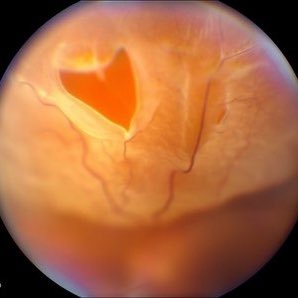

٤. انفصال الشبكية

العلاج: غالب الحالات تعالج جراحياً